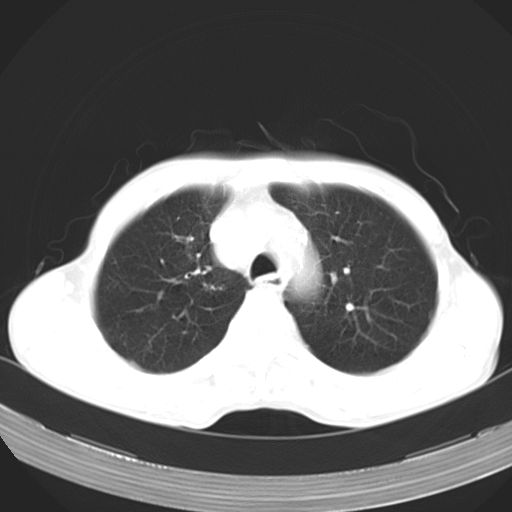

以下是引用苯小孩在2007-5-24 12:47:00的发言:[br]右侧肺门处不均匀密度软组织块影,远端肺组织见斑片模糊影,纵隔内淋巴结明显肿大,边界不清.<纵隔窗第12层面支气管内似见软组织结节>[br]考虑:1、右侧中央性肺癌并阻塞性肺炎并纵隔淋巴结转移可能性大.建议强化或纤支镜进一步检查.[br]2、隆突下淋巴结肿大/食道病变?请做鉴别检查.

以下是引用zhangzhongshou在2007-5-24 12:55:00的发言:[br]1、右肺中叶中心型肺癌并右肺门、隆突下、纵隔淋巴结转移。右肺中叶阻塞性肺炎。

以下是引用jw-830在2007-5-24 15:24:00的发言:[br][br] [br] 考虑右肺中央型肺癌并阻塞性炎症,右肺门及纵隔淋巴结转移。 [br] [br][br]